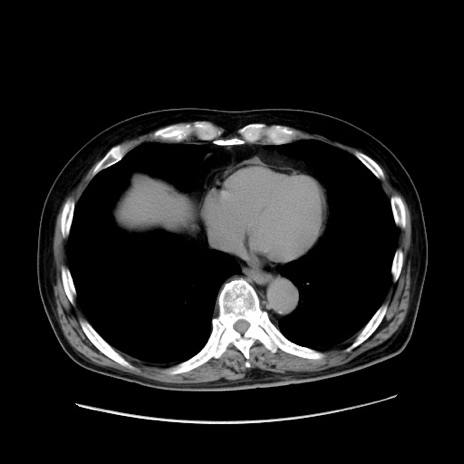

症例30(横断像)

【症例】80歳代男性

【主訴】臍周囲痛

【現病歴】約6時間前から臍下部痛が出現。次第に腹部膨隆・背部痛も生じてきたため来院。背部痛の場所は変化しない。

【身体所見】意識清明、BT 36.3℃、BP  131/87mmHg、P 87bpm、SpO2 100%(RA)、臍周囲自発痛・圧痛あり、反跳痛なし、自発痛部位に一致して板状硬あり、腹部膨隆、腸雑音減弱、CVA tenderness両側陰性。

【データ】WBC 19600、CRP 0.33